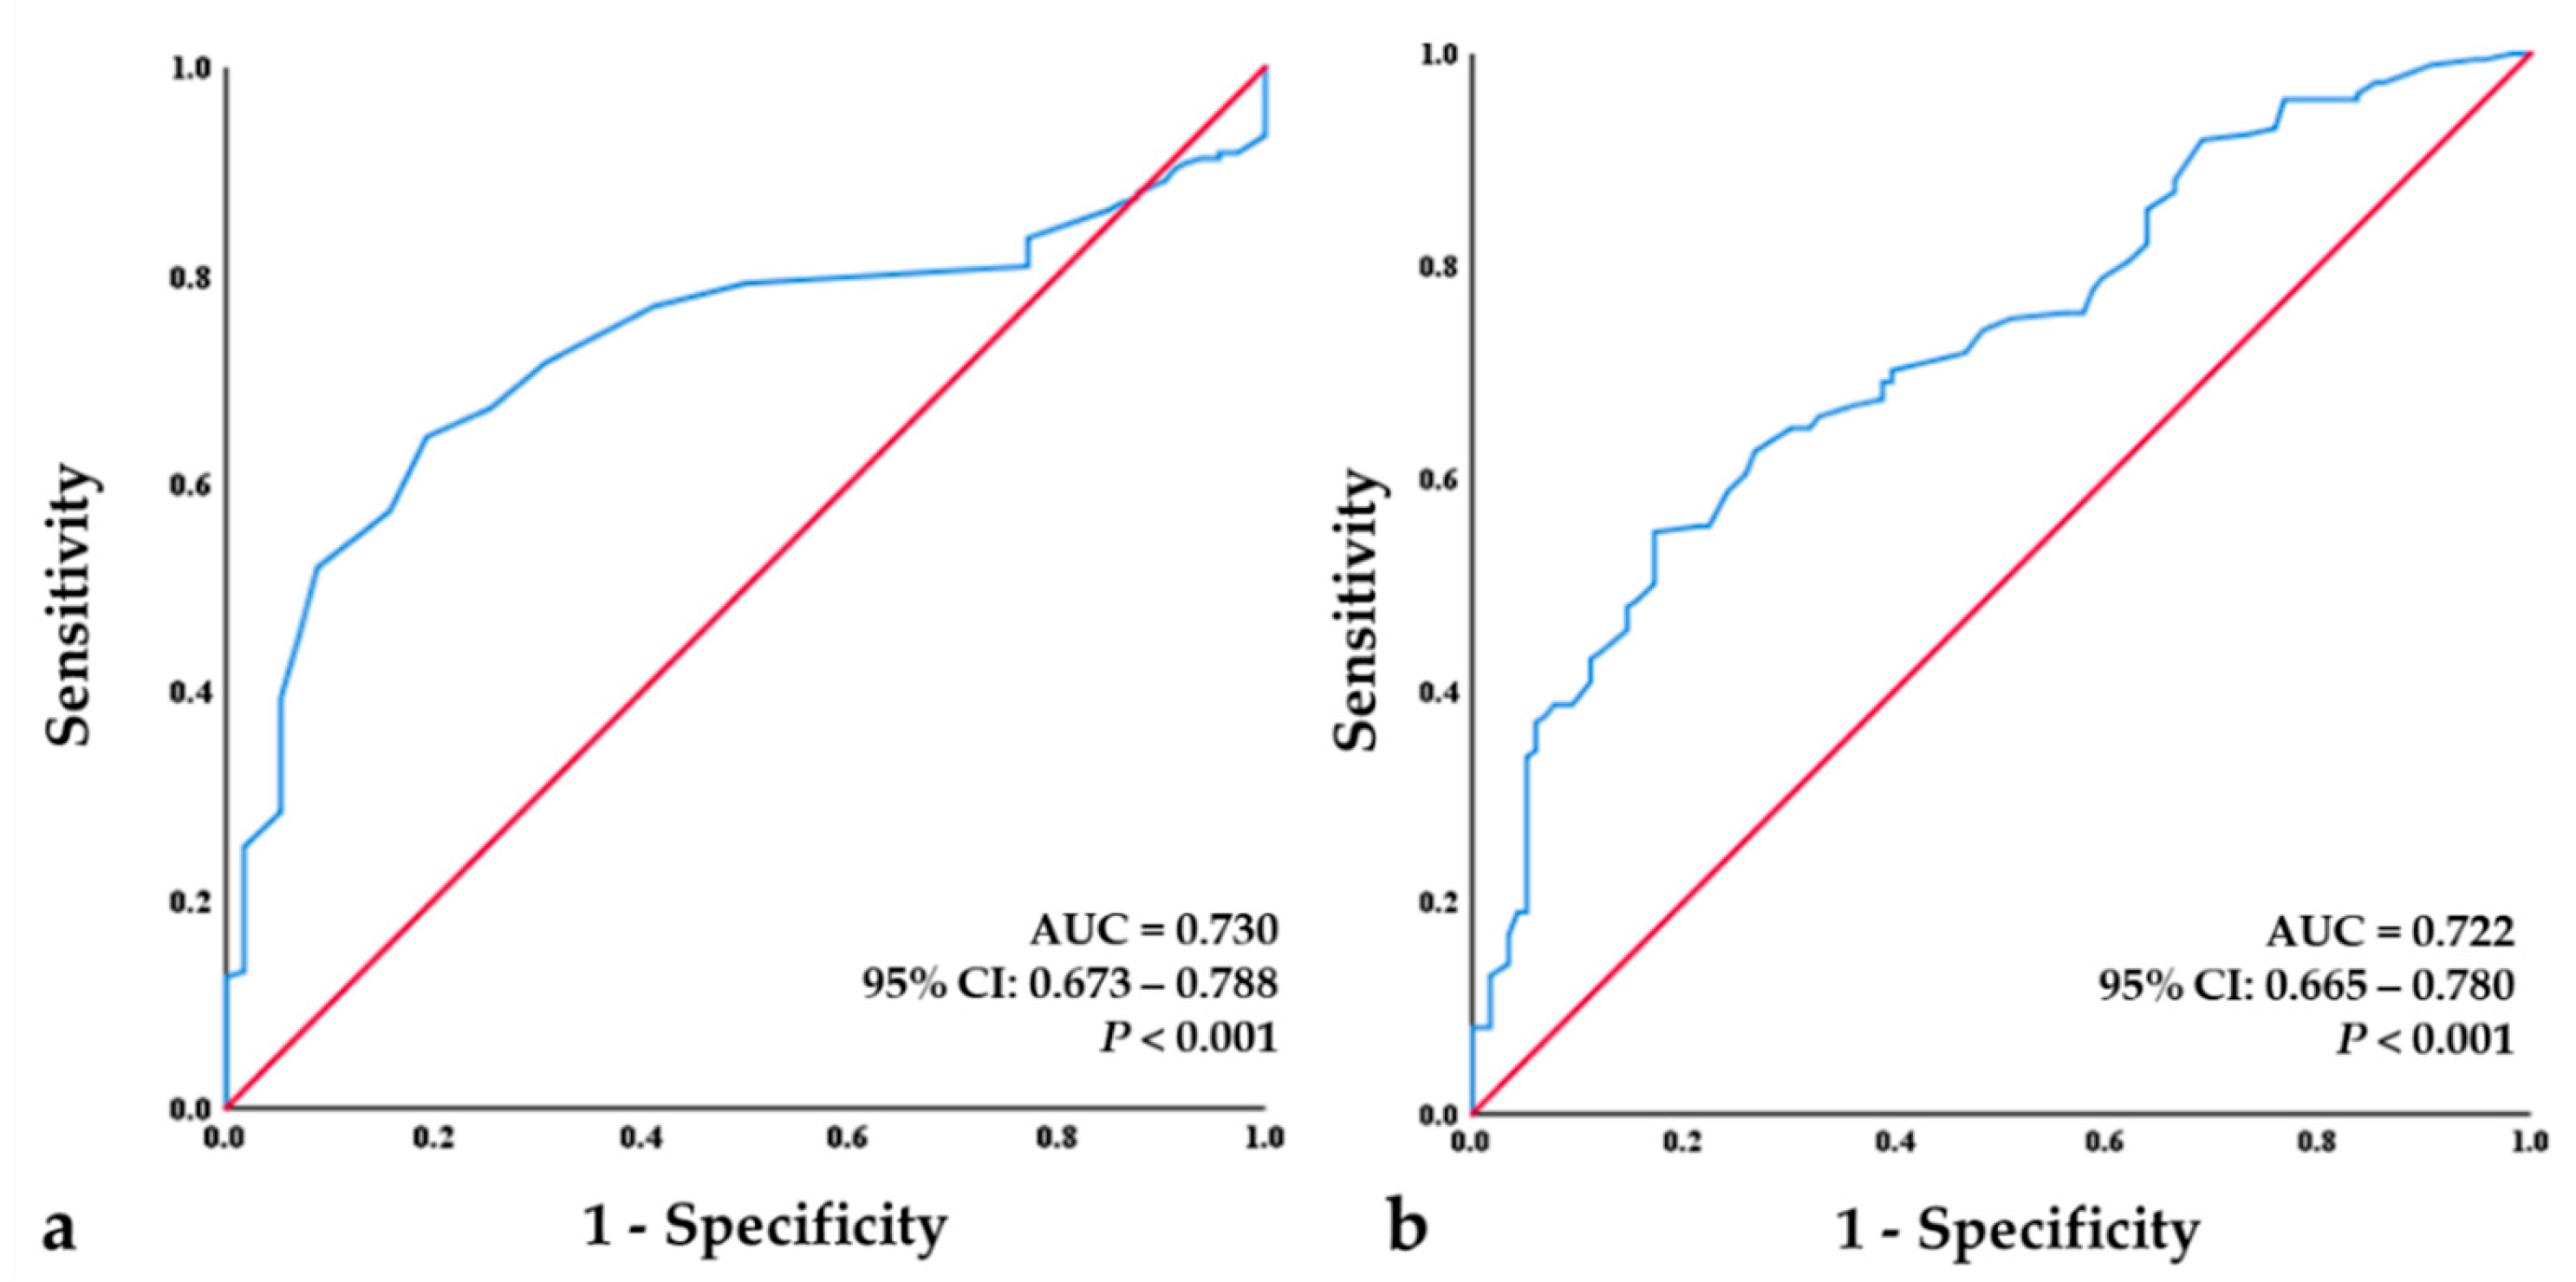

3.5. Logistic Regression Analysis for Bisphosphonate Treatment Failure